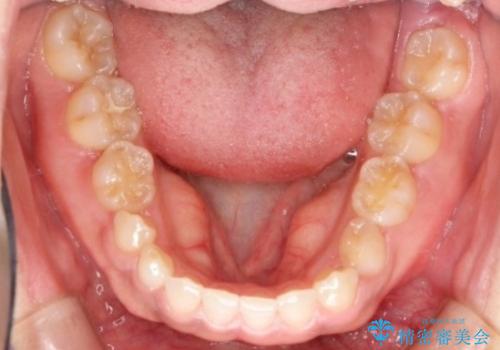

- 後続永久歯が欠損した患者様です。

矯正治療にて歯並びを改善したのち、インプラントにて咬合回復を行う治療計画としました。

捻転が強い部分だけはワイヤーの部分矯正で対応しております。